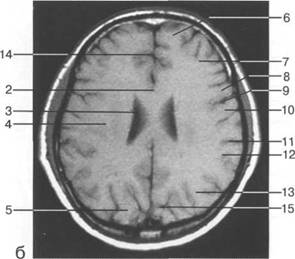

рога боковых желудочков; б - через структуры задней череп 13513u2010n 85;ой ямки.

IV IV IV IV III IV

височная доля; 17 - полушарие мозжечка; 18 - |